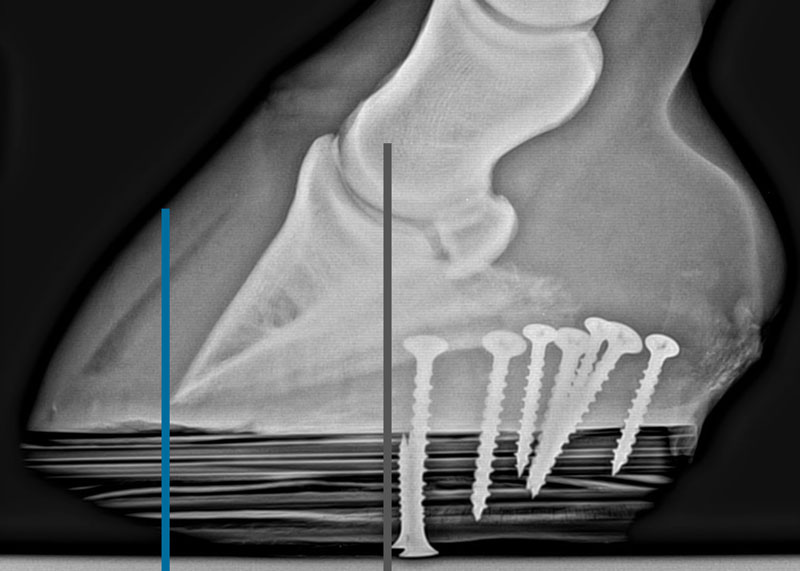

Wooden shoe applied to the foot. Note the beveled perimeter of the shoe and the point of breakover.

IMAGE COURTESY OF STEPHEN O'GRADY, DVM

Radiograph shows the biomechanics of the shoe. Gray line is center of rotation and blue line is point of breakover.